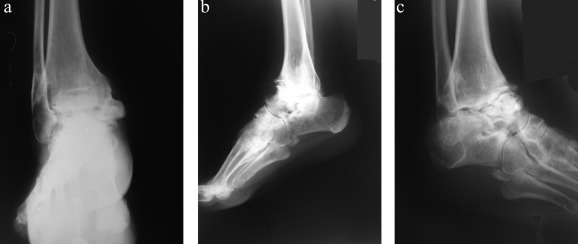

(a–c). Preoperative anteroposterior-lateral and oblique X-ray views of ...

Fig. 1.

(a–c). Preoperative anteroposterior-lateral and oblique X-ray views of 56-year-old female ankle arthrosis patient.